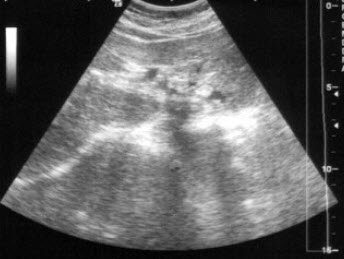

20、单项选择题

患者女36岁,反复上腹部疼痛不适数10年,偶尔皮肤、巩膜黄染。B超检查如图所示,根据超声声像图,诊断为()

A.左肝内胆管癌

B.左肝内胆管蛔虫

C.左肝内胆管胆泥淤积

D.左肝内胆管结石

E.左肝钙化灶